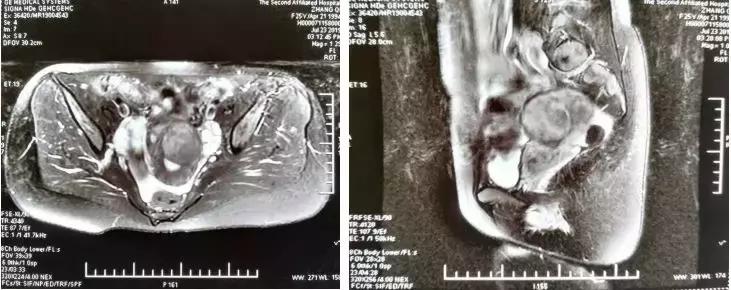

下面四组影像学资料为其中一名子宫肌瘤患者在治疗前、治疗中以及治疗后的影像学表现。

术前核磁提示T2高信号